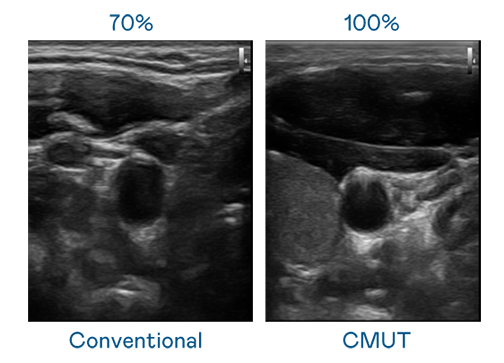

CMUT 技术是一种用电容式微机电元件来产生超音波讯号的技术。与传统 PZT 压电式技术相比,CMUT 频宽增加 30%,更宽频的超音波讯号让影像解析度大幅提升,是实现高影像品质医疗超音波扫描、促进精准医疗发展的关键技术。

大频宽带来超清晰影像

超音波影像的解析度高低,首先取决于探头能发出的讯号频宽。尊龙时凯人生就是搏官网 CMUT 可提供高清晰的超音波讯号,提供高频宽、高灵敏度、影像纹理细节更高的超音波影像,协助医护人员缩短影像判读时间及利用精准的医疗影像进行诊断。